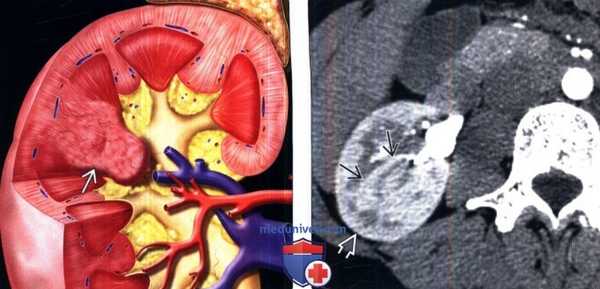

(Слева) КТ с контрастированием, коронарный срез, проекция максимальной интенсивности: у этого же пациента обнаружена «добавочная» почечная артерия нижнего полюса, которая представляется близко расположенной по отношению к пиелоуретеральному сегменту. Сосуды редко становятся причиной обструкции пиелоуретерального сегмента, однако их наличие необходимо учитывать при планировании вмешательств на пиелоуретеральном сегменте.

(Справа) При ретроградной пиелографии у этого пациента выявлен резкий переход от мочеточника нормального калибра к расширенной почечной лоханке на пиелоуретеральном сегменте. Обратите внимание на разбавление введенного контраста (он поступает в почечную лоханку в виде струи).

(Слева) На рисунке показано объемное расширение коркового вещества почки между верхней и средней чашечками.

(Справа) КТ, аксиальная проекция, кортико-медуллярная фаза контрастирования: дорсальная половина межполюсной области почки, контрастируемая аналогично корковому веществу почки. На последующих фазах выявлено гомогенное контрастирование почки.